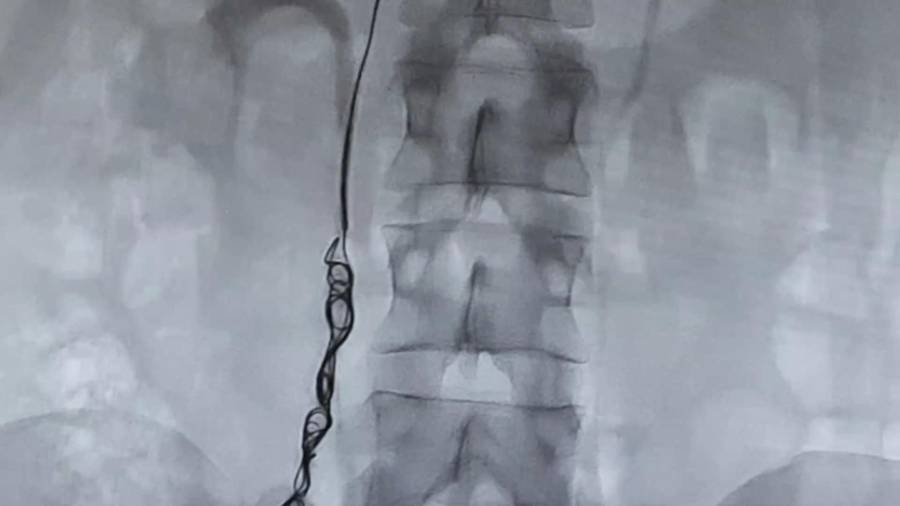

- Arteriography

A minimally invasive diagnostic technique providing anatomical and dynamic information about arteries. It allows immediate treatment with angioplasty when necessary.

- Phlebography

A minimally invasive diagnostic test offering high-quality images of vein morphology and flow. Pelvic or iliocavography phlebography can measure pressure gradients and perform embolization treatments during the same session.